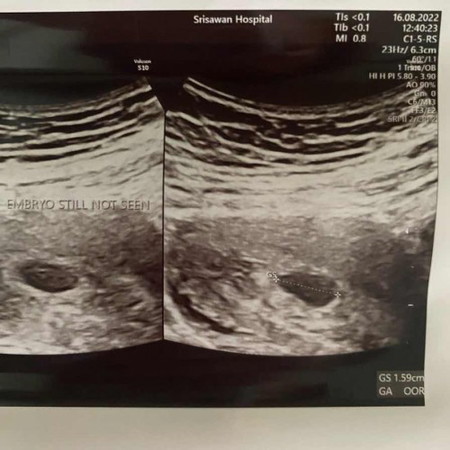

ตรวจครรภ์ไม่เจอตัวเด็ก

มีแม่ๆคนไหนตรวจครรภ์แล้วไม่เจอน้องมั้งค่ะ จากที่นับจากประจำเดือนล่าสุดน้องน่าจะ 7-8 week แล้ว หมอนัดให้ไปตรวจอีกวันที่ 30 ส.ค. นี้กลัวมากเลยค่ะ😔 มีแม่ท่านไหนเจอน้องช้าบ้างค่ะ

เป็นเหมือนกันค่ะ ซาวด์ครั้งแรก 2 ส.ค. เจอแต่ถุงกับไข่แดง หมอบอกว่าอาจจะท้องลม หรือตัวอ่อนหยุดเจริญเติบโต หรือนับวันคาดเคลื่อน ให้รอ 2 สัปดาห์มาซาวด์ใหม่ สรุปว่าเมื่อวานไปซาวด์ใหม่ เจอตัวเด็กแล้วค่ะ อย่าเพิ่งคิดมากนะคะ ✌️

ไม่เจอเหมือนกันเลยค่ะ หมอจะให้ขูดมดลูกเลย เราขอรออีก2อาทิตย์ นัดอีกที 31ส.ค. กังวลมากตอนนี้